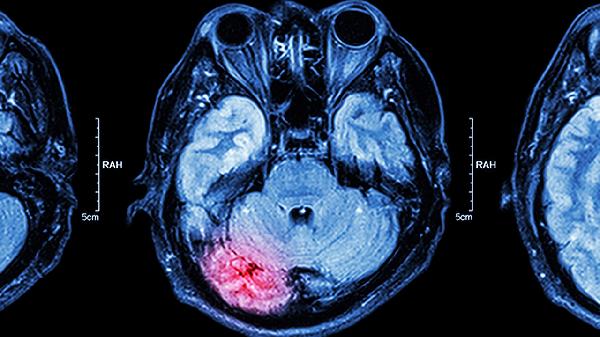

脑供血不足可能由动脉粥样硬化、颈椎病、高血压、心脏疾病、血液成分异常等原因引起。脑供血不足通常表现为头晕、头痛、视物模糊、肢体麻木、注意力不集中等症状。

动脉粥样硬化是脑供血不足的常见原因,可能与长期高脂饮食、吸烟等因素有关。血管壁脂质沉积导致管腔狭窄,影响脑部血液供应。患者可能出现短暂性脑缺血发作,表现为突发性眩晕或言语障碍。治疗可遵医嘱使用阿托伐他汀钙片、硫酸氢氯吡格雷片、尼莫地平片等药物控制病情,同时需调整饮食结构并戒烟限酒。

脑供血不足患者应保持规律作息,每日进行30分钟有氧运动如快走或游泳,饮食注意低脂低盐,多摄入深海鱼、西蓝花等富含不饱和脂肪酸和抗氧化物质的食物。避免突然起身或过度劳累,气候变化时注意头部保暖。若症状反复发作或加重,应及时进行经颅多普勒超声或脑血管造影检查,明确病因后针对性治疗。